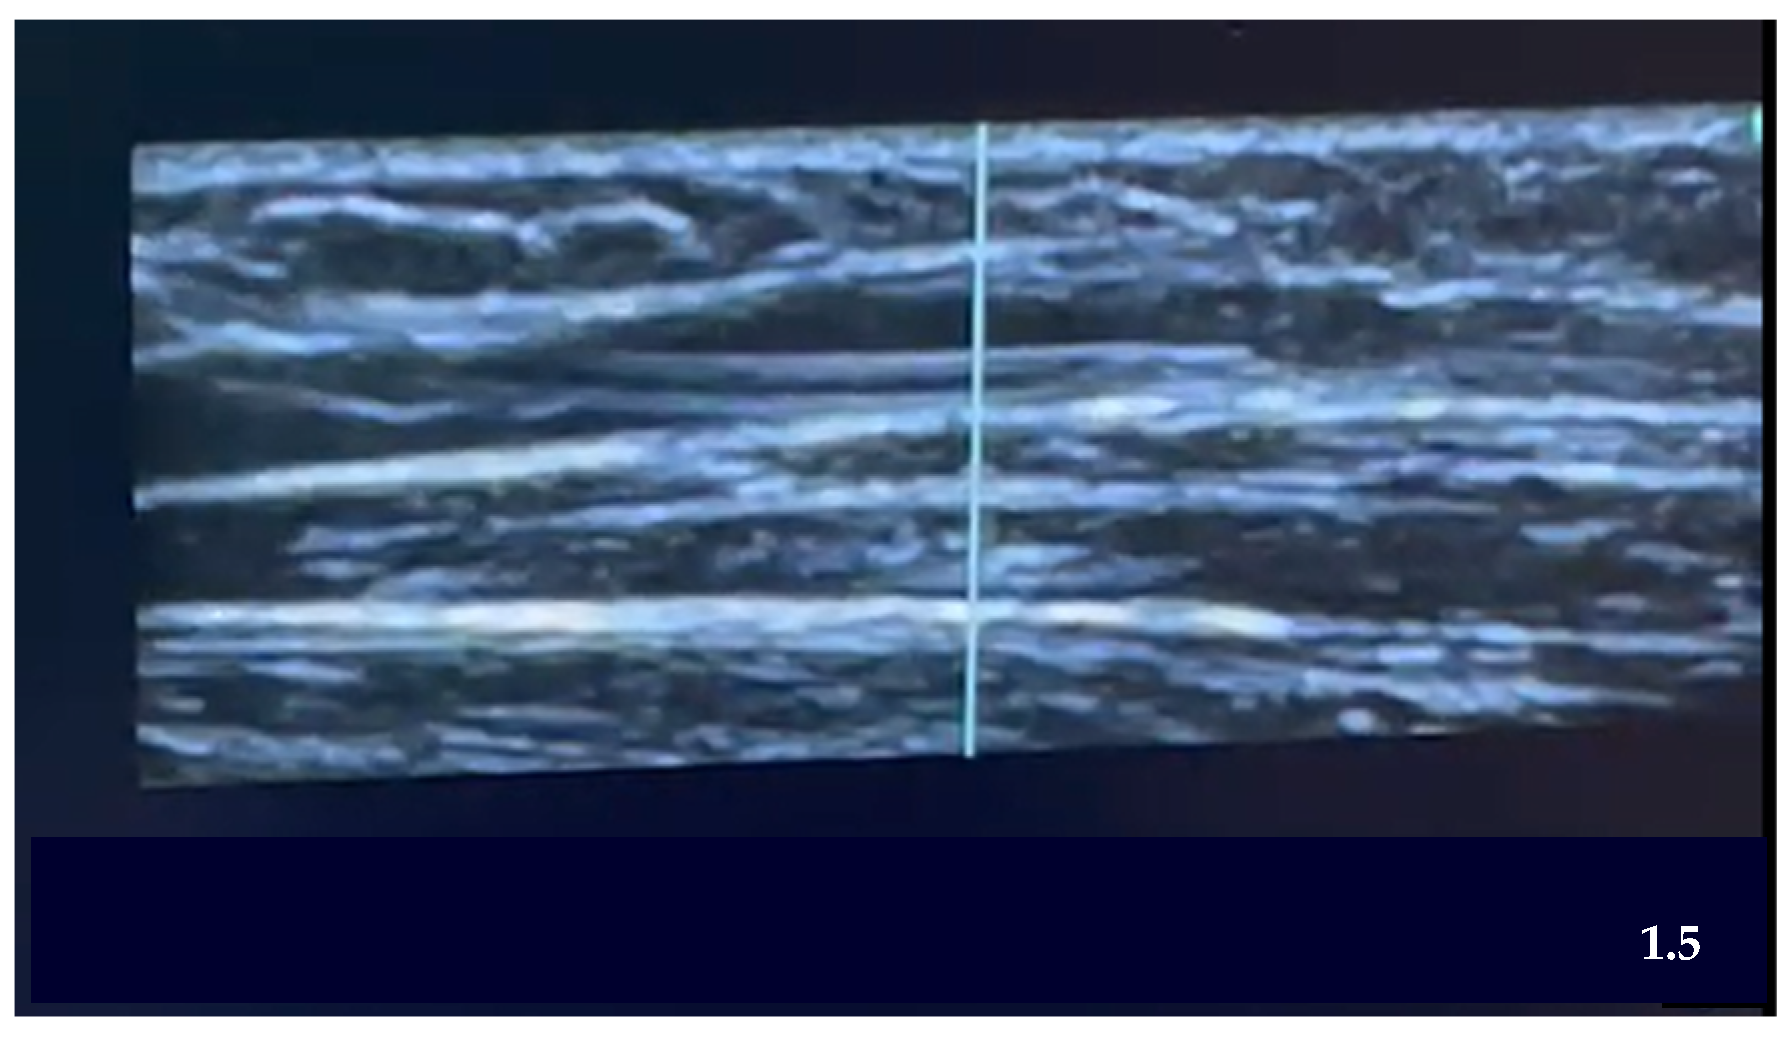

| STEP 6 | Ultrasound-guided puncture:

| Transducer placement | Longitudinal, transversal, none |